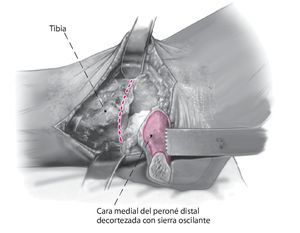

Fig. 5 Decortización de la cara medial del peroné distal con sierra oscilante. Esto aumenta la potencia biológica de la refijación.